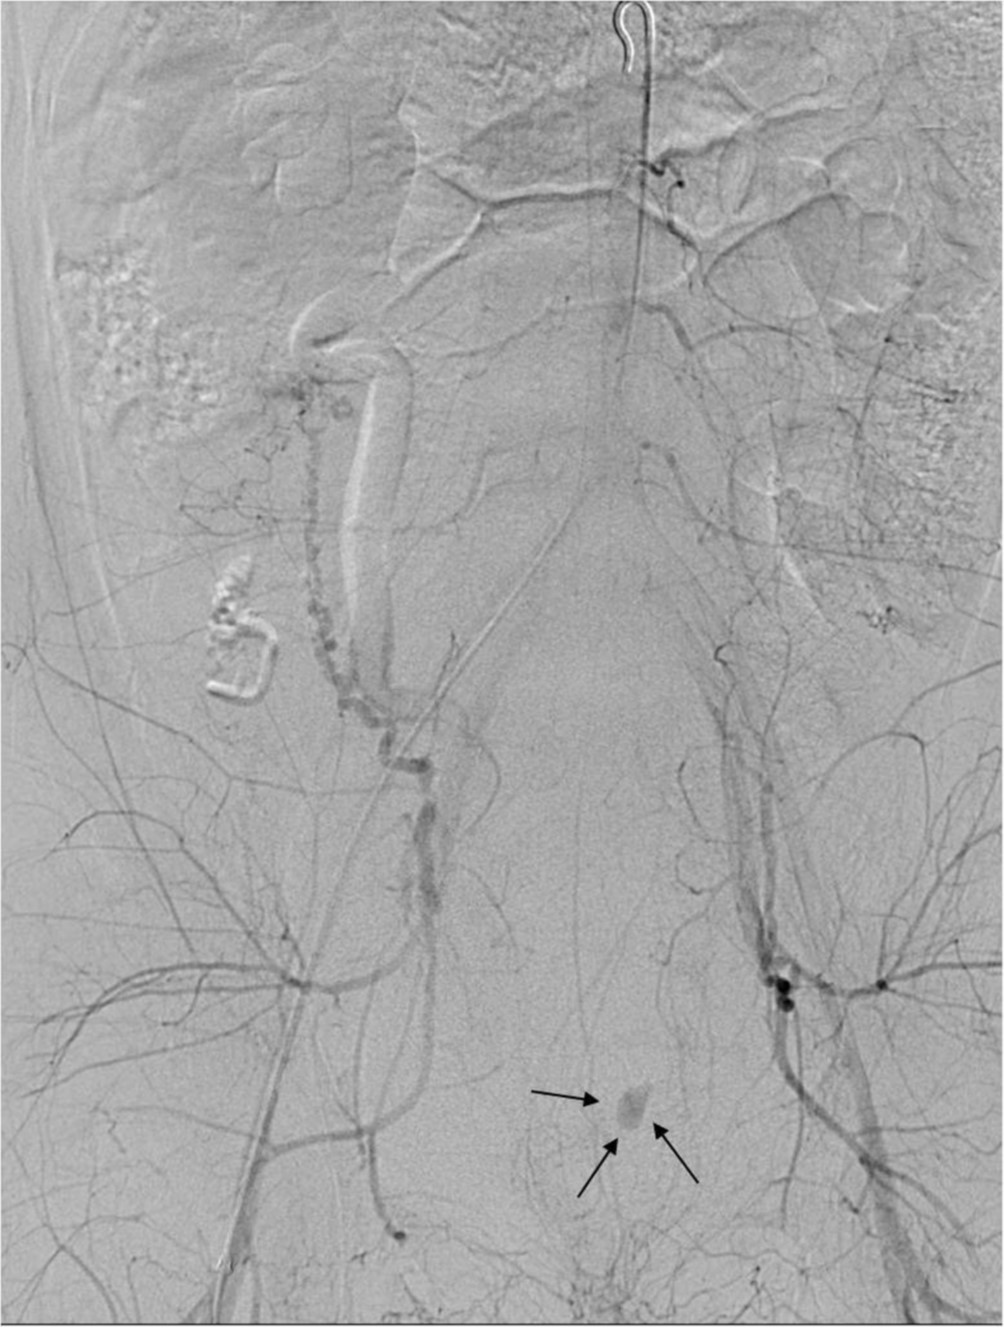

Fig. 2.

Pelvic angiogram shows extravasation of contrast media in the left pelvic cavity(arrows).

자궁동맥조영술상 비대해진 양측 자궁동맥이 관찰되었으나(Fig. 1), 혈류 유출은 없었다. 양측 자궁동맥을 gelfoam을 이용하여 색전술을 시행하였으며, 시행 후 골반동맥조영술에서 양측 자궁동맥의 혈류는 모두 소실되었으나 좌측 골반강에 조영제 혈관외 유출이 관찰되었다(Fig. 2).

초음파 유도 하에 우측 대퇴동맥을 천자하여 5F Accu-Sheath Introducer System(Sungwon Medical Co, Cheongju, Korea)을 삽입하였다. 0.035-inch 유도철사(Terumo, Tokyo, Japan)와 5F pigtail catheter(Cook, Bloomington, USA)를 이용하여 복부 대동맥에서 골반동맥조영술을 시행하였으며 비대해진 양측 자궁동맥을 확인하였다. 5F Omni-Flush Catheter(Angiodynamics, Queensbury, USA)를 이용하여 양측 내장골동맥을 선택하여 혈관조영술을 시행하였고, 3F Renegade catheter(Boston Scientific, Natick, USA)와 0.016-inch Fathom guidewire(Boston Scientific, Natick, USA)로 자궁 동맥을 선택하였다. 자궁동맥은 1-2mm 크기의 gelatin sponge(Cutanplast, Mascia Brunelli, Milan, Italy)를 이용하여 색전하였고, 자궁동맥 내에조영제의 정체가 보일 때까지 색전술을 시행하였다. 색전술 후 시행한 골반동맥조영술에서 양측 혈류는 모두 소실되었으나 좌측 골반강에 조영제 혈관 외 유출이 관찰되었다. 좌측 외장골동맥조영술시 아래배벽동맥 분지에서 가성동맥류가 있었으며(Fig. 3), N-butyl-2-cyanoacrylate(Histoacryl, B. Braun, Melsungen,Germany) 와 리피오돌 1:4 혼합액으로 색전술을 시행하였다. 다시 시행한 혈관조영술에서 가성동맥류가 완전히 폐색된 것을 확인하였다(Fig. 4). 시술 12시간 후 환자는 다시 질출혈 발생하였으며 수액공급 및 수혈 시행 후에도 혈압 80/55mmHg, 맥박 98회/min, 혈색소 6.4g/dL로 감소하여 응급 자궁동맥 색전술 다시 시행하였다. 골반동맥조영술 시행 시 우측자궁동맥에서 조영제 혈관외 유출이 관찰되었으나(Fig. 5) 혈관연축으로 인하여 자궁동맥 선택이 어려워 자궁동맥 입구에서 300-500μm polyvinyl alcohol particles(Cook, Bloomington, USA)과 gelatin sponge를 이용하여 색전술 시행하였다. 시술 후 시행한 혈관조영술에서 우측 자궁동맥 폐색과 조영제 혈관외 유출이 사라진 것을 확인하였다(Fig. 6). 색전술 후 환자는 소량의 질출혈외 특별한 증상 없었으며 한달 뒤 하복부 통증과 다량의 질출혈로 내원하였다. 조영증강 복부 CT상 자궁내막과 자궁근층에 조영 증강이 거의 보이지 않고 테두리 조영증강을 보였다(Fig. 7). 보존적 치료에도 증상 계속되었으며 지속적 출혈, 감염의 위험 등 있어 자궁절제술 시행하였다. 병리 소견상 자근근층에 괴사와 출혈이 있었다.